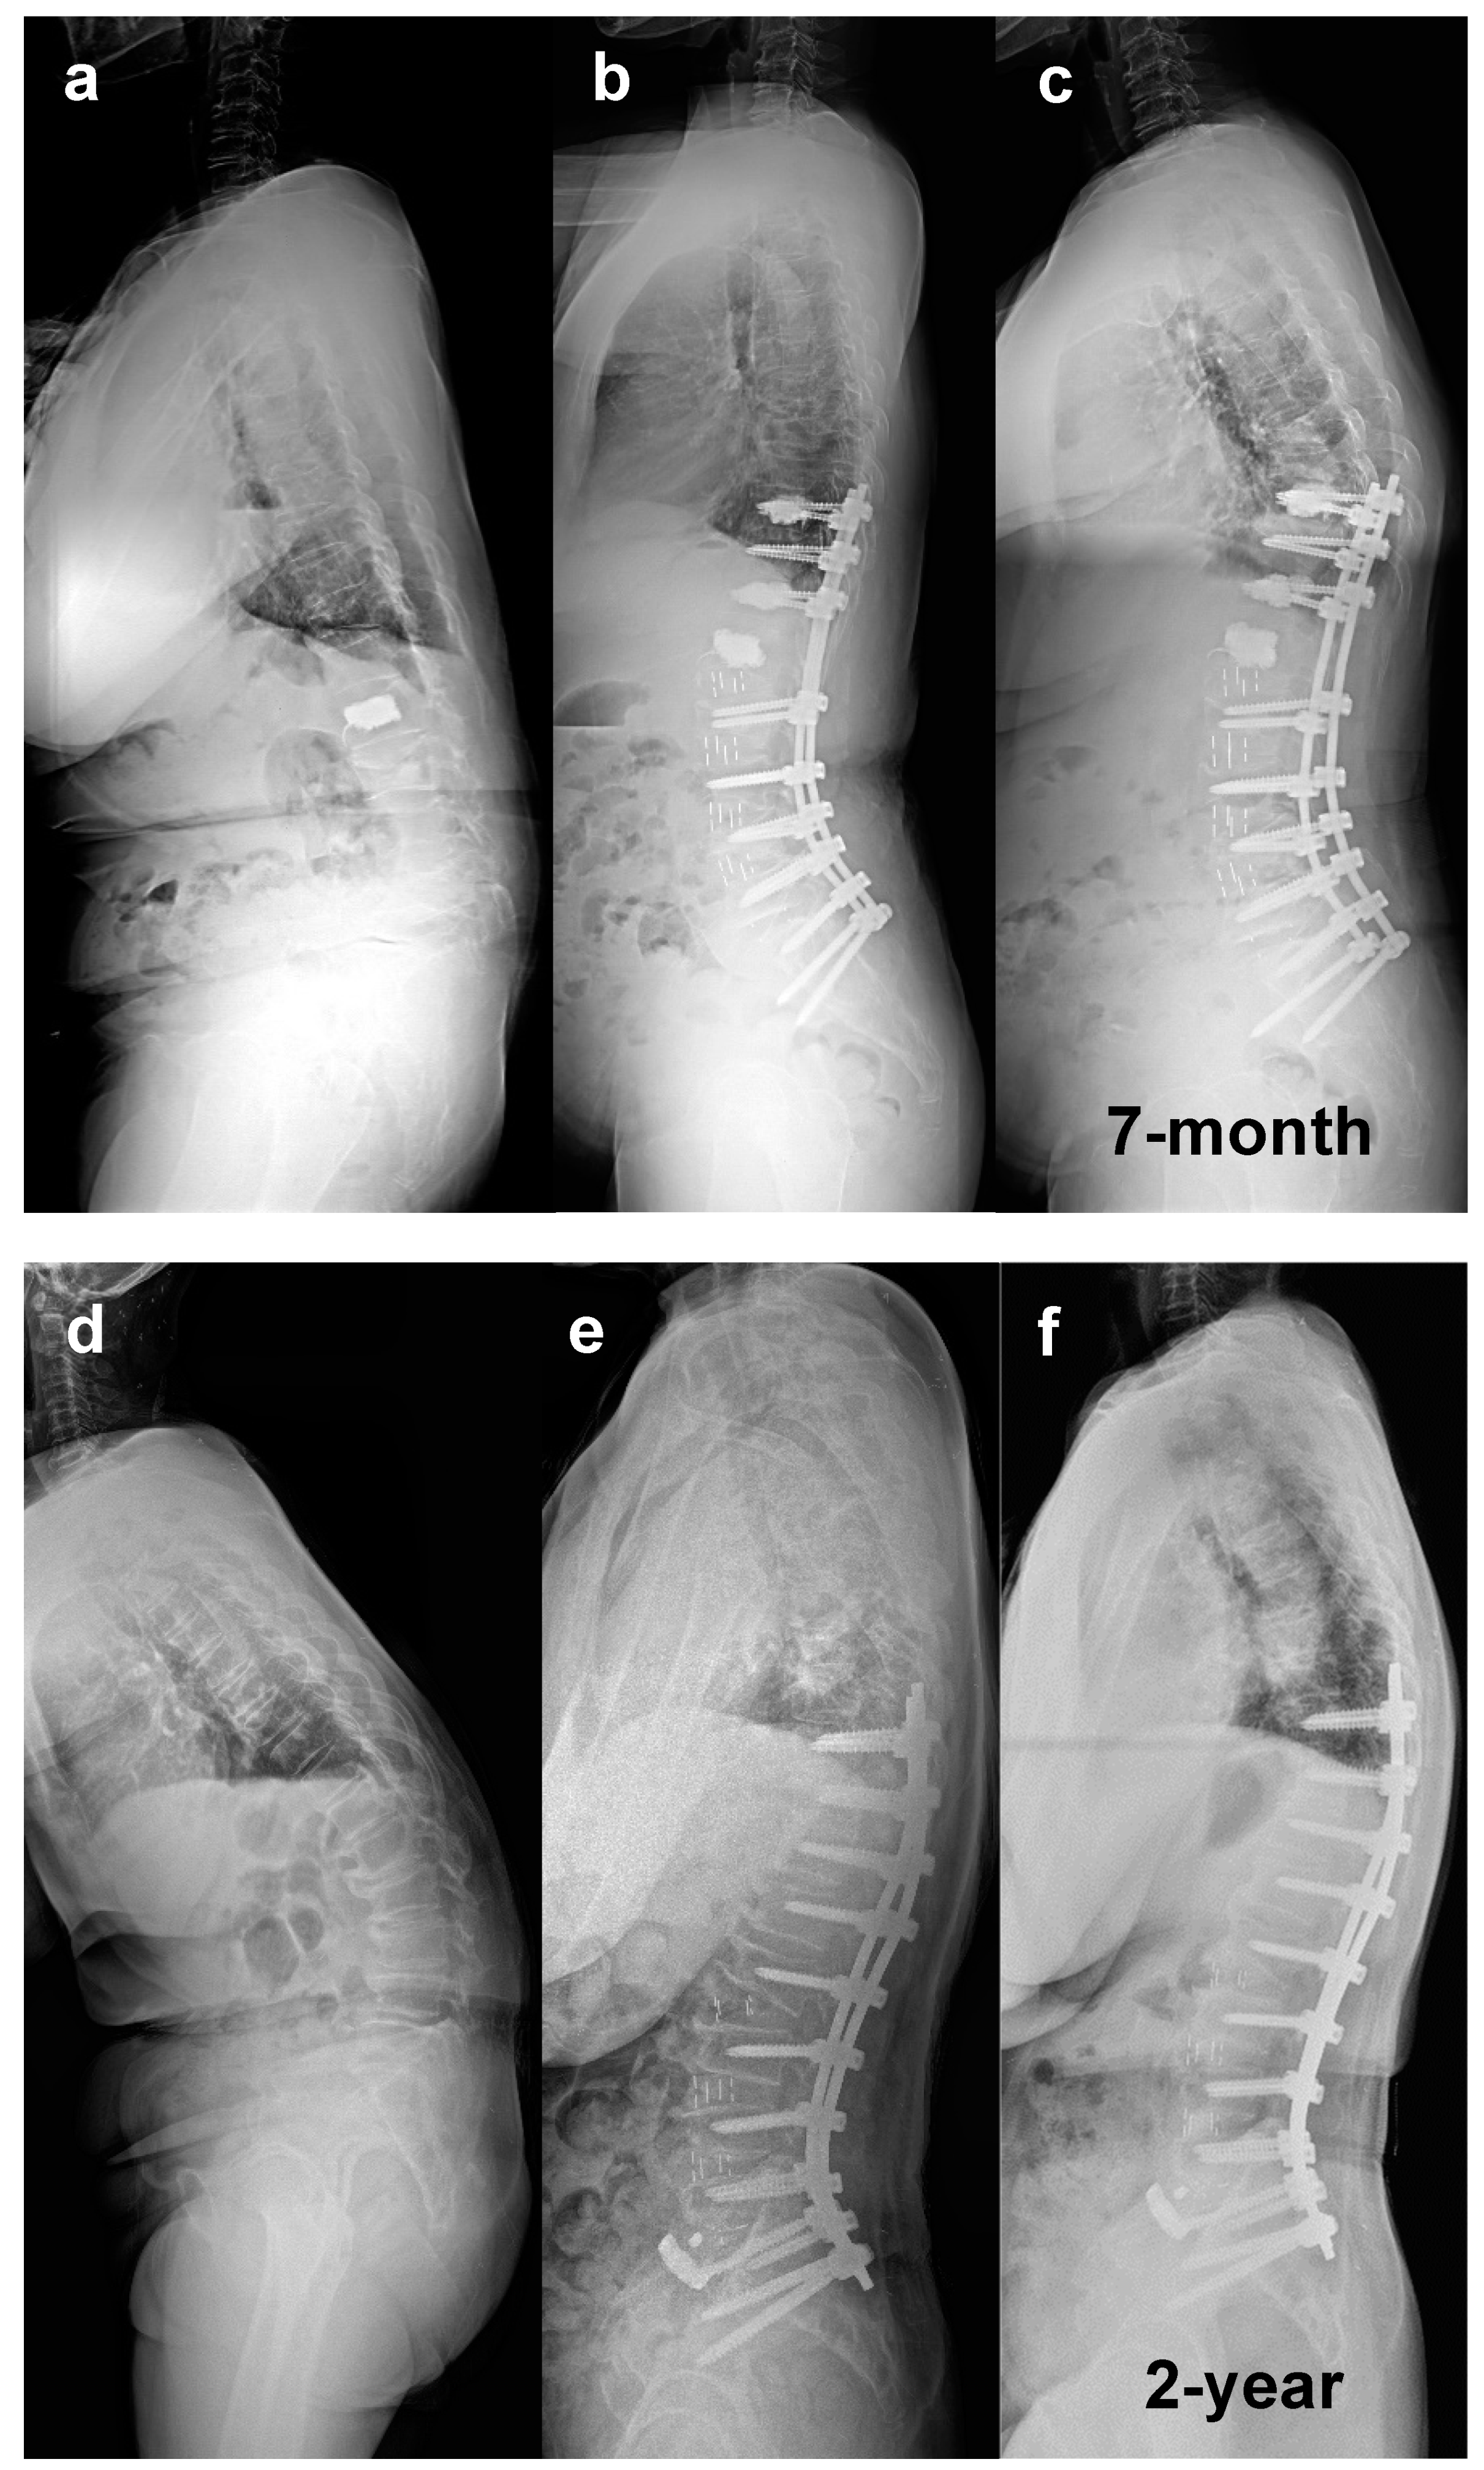

- Park, S.W.; Ko, M.J.; Kim, Y.B.; Le Huec, J.C. Correction of marked sagittal deformity with circumferential minimally invasive surgery using oblique lateral interbody fusion in adult spinal deformity. J Orthop Surg Res 2020, 15, 13–21. [Google Scholar] [CrossRef] [PubMed]